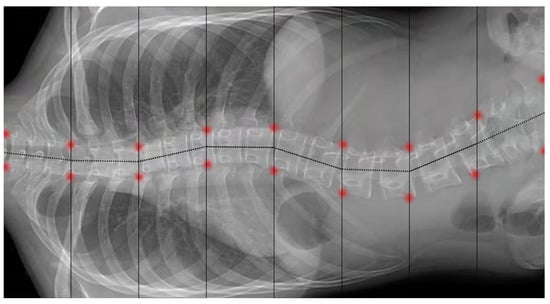

4.2.2. Locate the Landmark of the Spine to Measure the Cobb Angle